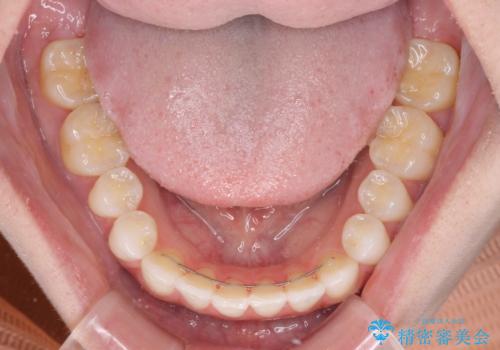

- 前歯の上下スペースによる話しにくさと顎への負担を気にして来院された患者様です。

インビザラインにより上顎の大臼歯を圧下し、上下の前歯の隙間を閉じていくこととしました。

上顎の奥歯を圧下させることで、上下前歯を接触させるように計画しました。

前歯が急に接触するようになり、慣れるまで時間がかかりましたが、前歯でものが咬めるようにもなり、患者様には大変満足していただきました。